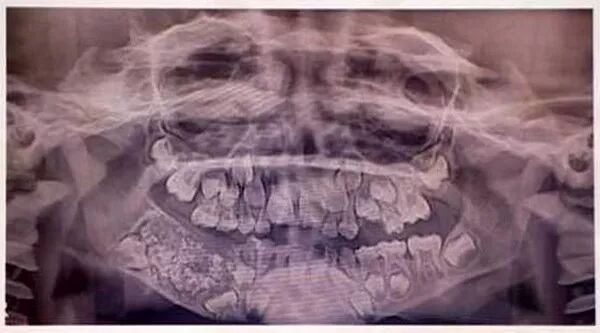

现年7岁的一名印度男孩自3岁起便向父母抱怨,他的下巴颏肿胀不适,可父母却一直以为这是孩子闹妖,没当回事。4年后,下巴异常增长的男孩终于被一位医生发现不妥。在X光片中,医生在其下巴的肿块内发现了数百个坚硬的阴影……当医生将这块大小约为5厘米宽、3厘米厚的肿块切开之后,里面竟藏着526颗大大小小的牙……医生表示:“所幸肿块并未与其他骨骼相连,手术很成功,孩子的下巴今后将与常人无异。”